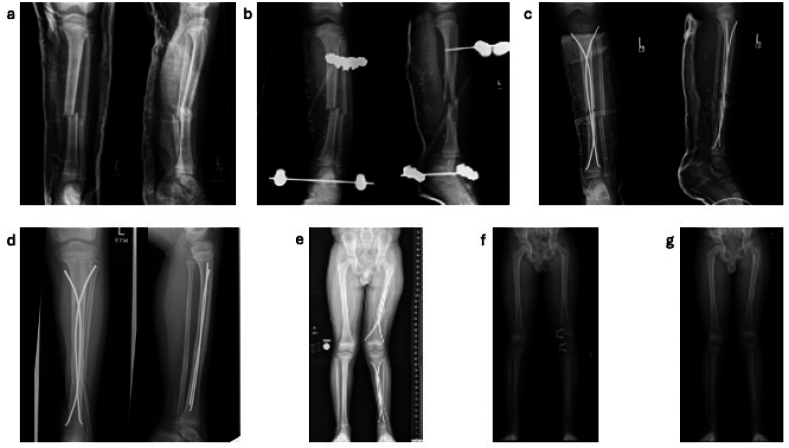

Abstract Image